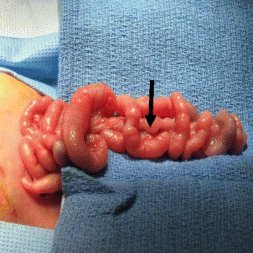

Jejunal Atresia

Apple Peel or Christmas Tree Seen in Jejunal Atresia